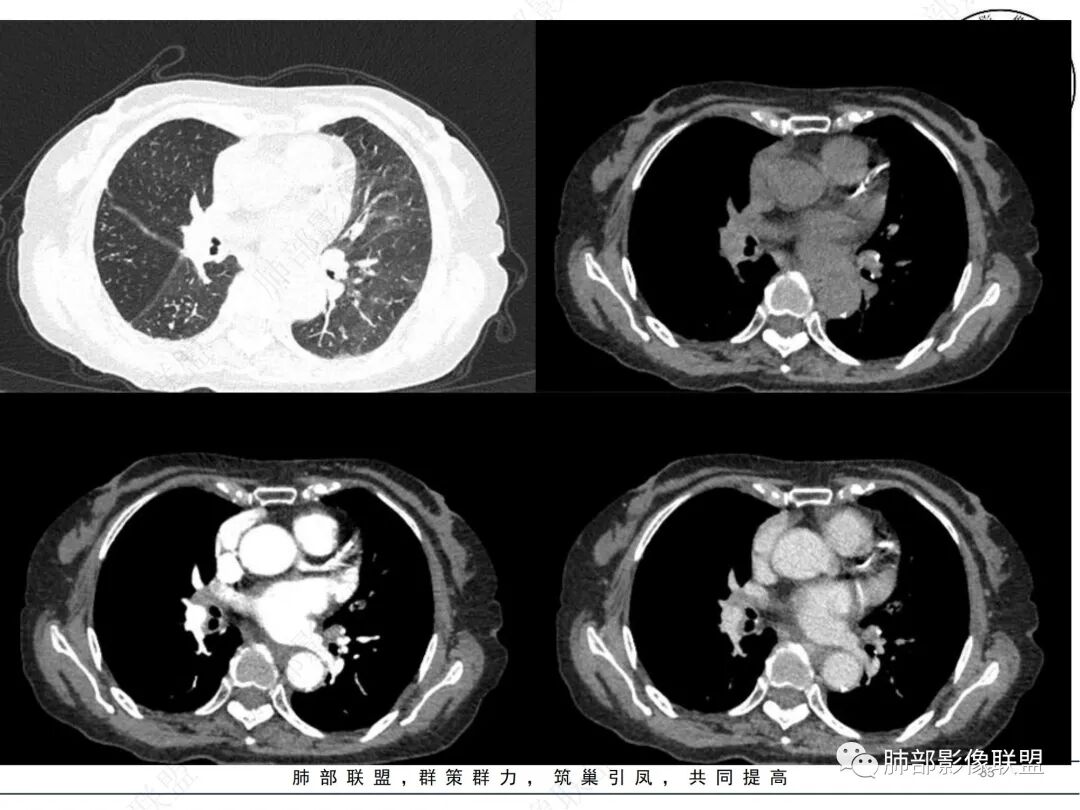

2. CT示右肺上叶多发斑片状实变影,结节影,集群散落,夹杂条索影,边界可分辨,有沿支气管血管束分布趋势,可见树芽征。病灶新旧不等、密度不均。右上叶支气管壁不均匀节段性增厚狹窄,斑点状钙化。纵隔旁部分肺组织含气不良,并显示轻度扩张支气管。病灶邻近胸膜增厚,轻度强化。

3.余双肺显示马赛克灌注、轻度气肿。双肺散在微小实行密度结节影,边界清楚。

4.纵隔多发增大淋巴结,部分融合、钙化。

成簇分布斑片影、结节影、树芽征,边界较清楚,新旧不等,节段性支气管壁增厚伴钙化,管腔狭窄,纵隔及肺门淋巴结增大钙化等都较符合“继发性肺结核、支气管内膜结核”诊断。